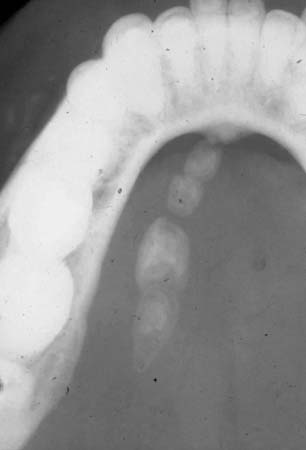

Occlusal radiographic film showing presence of multiple sialoliths in the left Wharton duct

From the personal collection of Dr A. Aguirre; used with permission